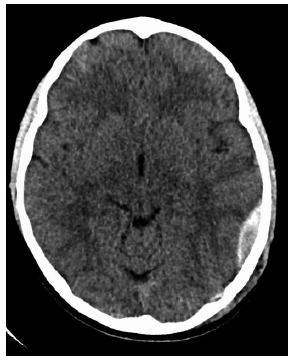

Considere a descrição e a imagem a seguir:

Menino sofreu queda há aproximadamente 4 horas. Estava andando de skate na rua e caiu de costas, no chão, e bateu a cabeça. Apresentou vômitos, está um pouco sonolento; fez a seguinte tomografia, sem contraste.

O diagnóstico é de hematoma